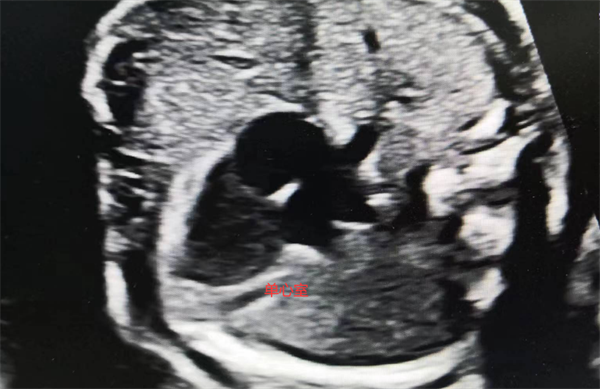

“听到这个消息的时候,我们看到了希望。”夫妻俩说。于是他们立即办理入院手续,入院后予完善检查。董完秀组织科内讨论,为保证母胎安全及减胎成功,提交了医务部组织MDT(多学科会诊),经过产前诊断中心、超声科、心理科以及产科团队共同讨论,制定了周密的治疗方案。于超声介入室在超声引导下行心脏畸形胎儿心内注射氯化钾减胎术,唐女士成功做了减胎术,过程顺利,监测正常胎儿胎心率正常,目前随访母胎良好。

而另外一名孕妈妈李女士(化名)在做NT的时候已提示存在异常风险,可李女士想再坚持一下。在孕近5个月(19周)进行系统彩超检查的时候再次提示其中一个胎儿脊柱裂结构异常,好在另一个胎儿目前是正常的。经多家医院系统B超均证实双胎之一胎儿畸形后,李女士同样在桂林市妇幼保健院接受了减胎术,目前随访母胎良好。